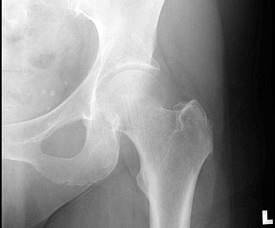

问题 图示股骨颈骨折为Garden第几型 ( )

选项 A、Ⅳ型 B、以上都不是 C、Ⅱ型 D、Ⅲ型 E、Ⅰ型

答案 E